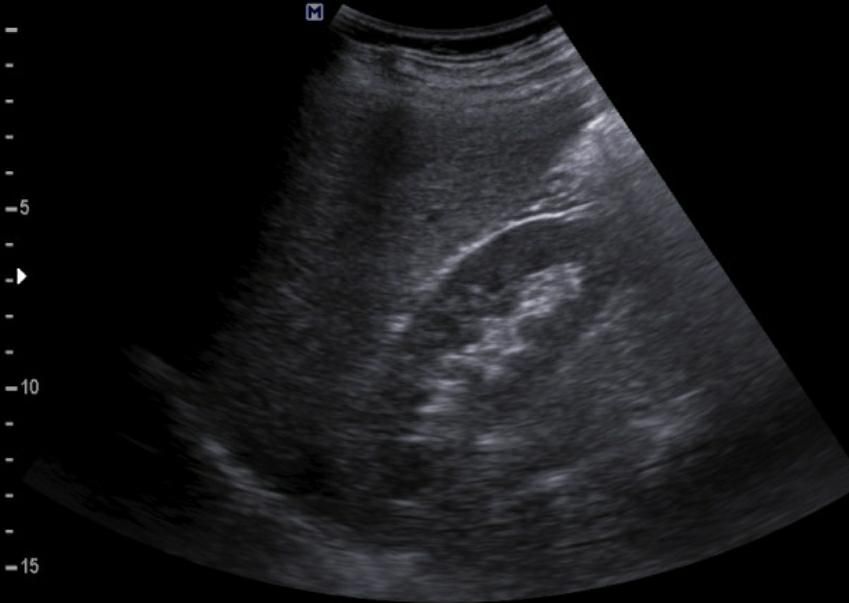

간에 혹이 있는건가요? 초음파 사진 봐주세요

간에 혹이 있는건지 맞다면 크기나 모양이 혈종인지 아이면 암으로 의심이 되는지 초음파 사진 봐주세요...ㅜㅜㅜ꼭 답변 부탁드립니다

• 4번 째 사진

간 초음파로만 봐서는 약간의 지방간이 관찰되지만 혈종으로 의심되지는

않으며 사진 우측에 보이는 동그란 부분은 장의 단면이 관찰되었을 가능성이

높은 것으로 보입니다